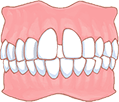

こんな症状ありませんか?

デコボコ

出っ歯

すきっ歯

受け口

開咬